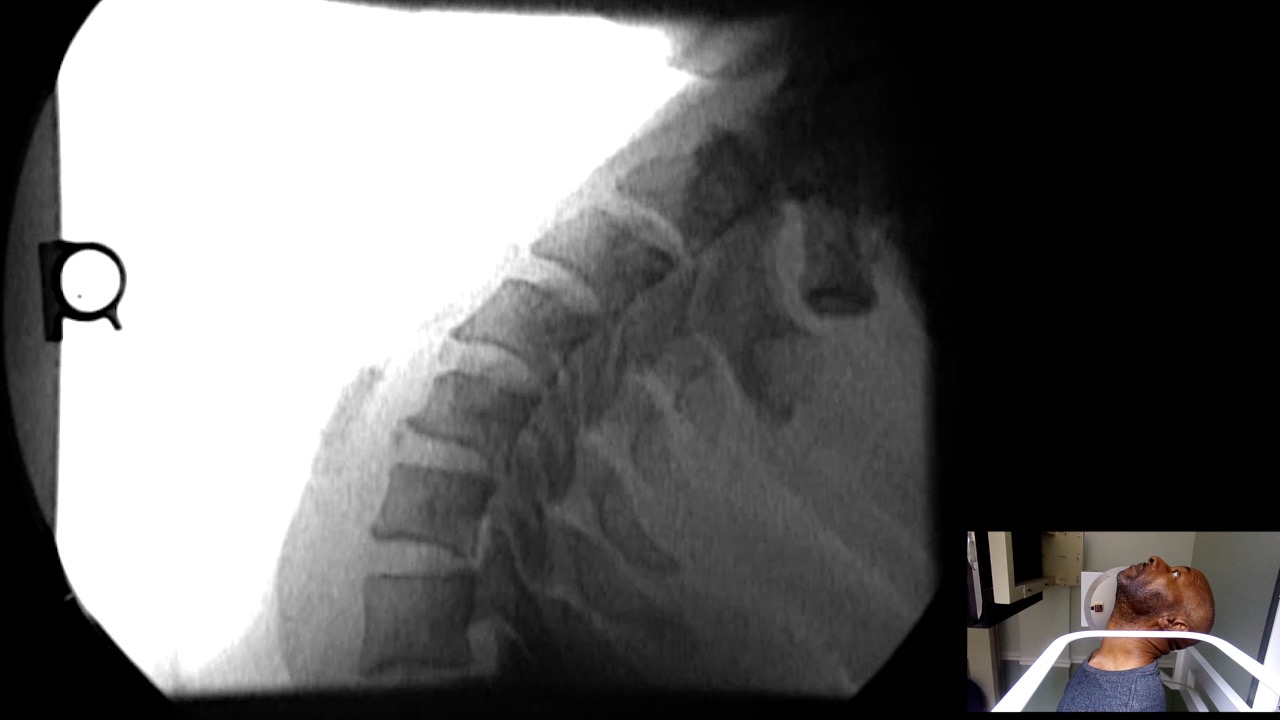

Image Name Image Type Image